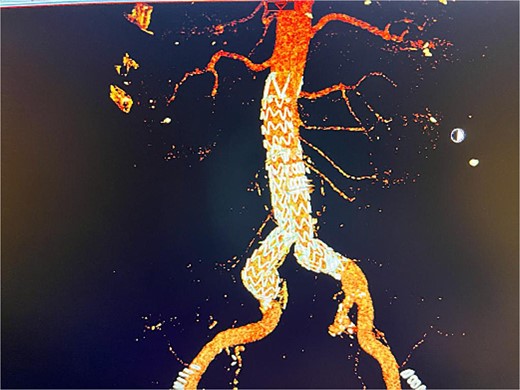

The patient presented 2 months after the initial procedure to the emergency department with burning pain and pallor in his right leg. On physical examination, there was pallor below the knee in addition to loss of pulsation. Physical examination revealed loss of pulsation below the knee. CT angiography (CTA) showed total occlusion of the popliteal artery without any endoleaks, prompting an urgent transpopliteal embolectomy. Trans-esophageal Echocardiography and CTA of the aorta were performed to rule out other sources of embolization, revealing a thrombus adherent to the wall distal to the stent graft (Fig. 3). The patient was started on warfarin.

CTA scan showing the floating thrombus distal to the right iliac artery stent, following the patient presenting with acute embolic ischemia in the right leg.

Despite these interventions, the patient experienced further episodes of acute limb ischemia (Fig. 4), leading to thrombolytic therapy a month later. This recurrence prompted a reevaluation of the treatment strategy. We considered extending the graft limb, which would involve sacrificing the hypogastric artery, or using an iliac artery extension with an iliac side branch. We ultimately chose the latter and implanted an E-iliac stent graft (Jotec ISB system) (Fig. 5a and b). Preservation of the hypogastric artery was prioritized, although extending into the external iliac artery would have been a viable alternative. However, the multidisciplinary team decided the preservation of the hypogastric artery would be more appropriate in this patient. The patient was discharged without anticoagulants.

Coronal view of CTA scan showing right femoral artery embolic obstruction